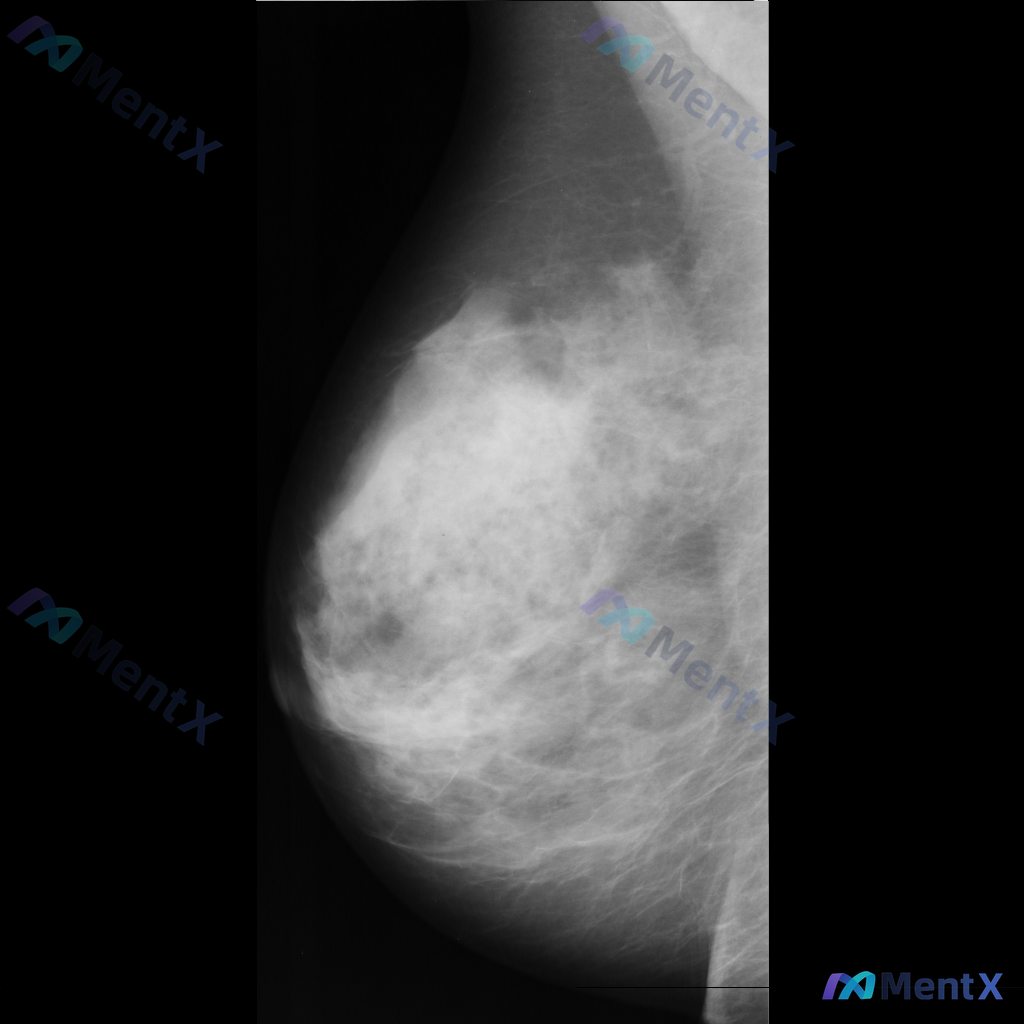

整理到一份乳腺钼靶的影像资料,大家可以一起讨论下: 主要影像表现:右侧乳腺后方(近胸壁处)可见一处局灶性不对称致密影,密度高于周围正常乳腺组织,边界模糊,同时伴有周围乳腺组织结构扭曲。 目前影像科考虑这处异常有可疑特征,需要进一步鉴别。 想问问大家,单看这组描述的话,第一反应会先往哪个方向考虑?后续...

整理到一张乳腺钼靶影像的异常表现,分享给大家讨论: 一侧乳腺可见不规则形高密度致密影,伴有明显的结构扭曲和局部腺体结构紊乱。 单看这组影像描述,大家会优先往哪种方向考虑?后续如果要进一步明确,你觉得哪些步骤比较关键?